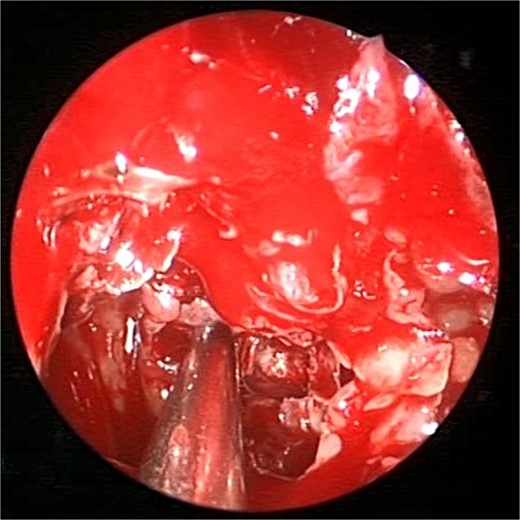

An asthmatic 42-years-old patient who was previously medically treated for allergic rhinitis with no significant improvement. A subsequent CT scan revealed isolated sphenoid sinus disease (Fig. 3). Intra-operative endoscopic findings revealed fungal mud and mucin (Fig. 4A and B) with post-operative (Fig. 4C) endoscopic finding of widely open, clean sphenoid sinus. Further histological examination of the specimen proved the diagnosis of eosinophilic AFS.

Coronal CT scan image showing complete sphenoid sinus heterogenous opacification.

Intra-operative (a, b, and c) endoscopic sphenoidotomy showing mud and mucin, with post-operative examination (d) of right optico-carotid recess showing wide and clean sphenoid sinus.